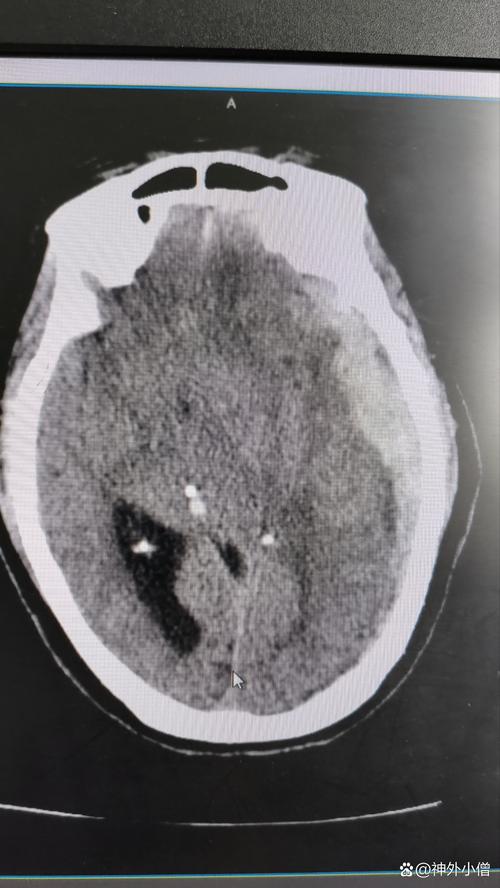

- 诊断: 一旦怀疑脑梗,医生会立即安排头部CT扫描(早期可能显示不清,但可排除出血)和磁共振成像,特别是DWI序列,能非常早期、准确地发现梗塞灶,CTA(CT血管造影)或MRA(磁共振血管造影)可以帮助评估血管有无狭窄或闭塞。